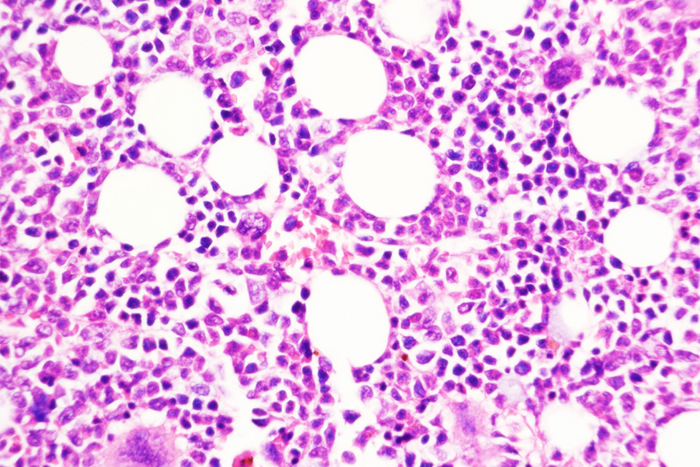

A type of chronic leukemia can simmer for many years. Some patients may need treatment to manage this type of blood cancer — called myeloproliferative neoplasms (MPN) — while others may go through long periods of watchful waiting. But for a small percentage of patients, the slower paced disease can transform into an aggressive cancer, called secondary acute myeloid leukemia, that has few effective treatment options. Little has been known about how this transformation takes place.

But now, researchers at Washington University School of Medicine in St. Louis have identified an important transition point in the shift from chronic to aggressive leukemia. They have shown that blocking a key molecule in the transition pathway prevents this dangerous disease progression in mice with models of the disease and in mice with tumors sampled from human patients.